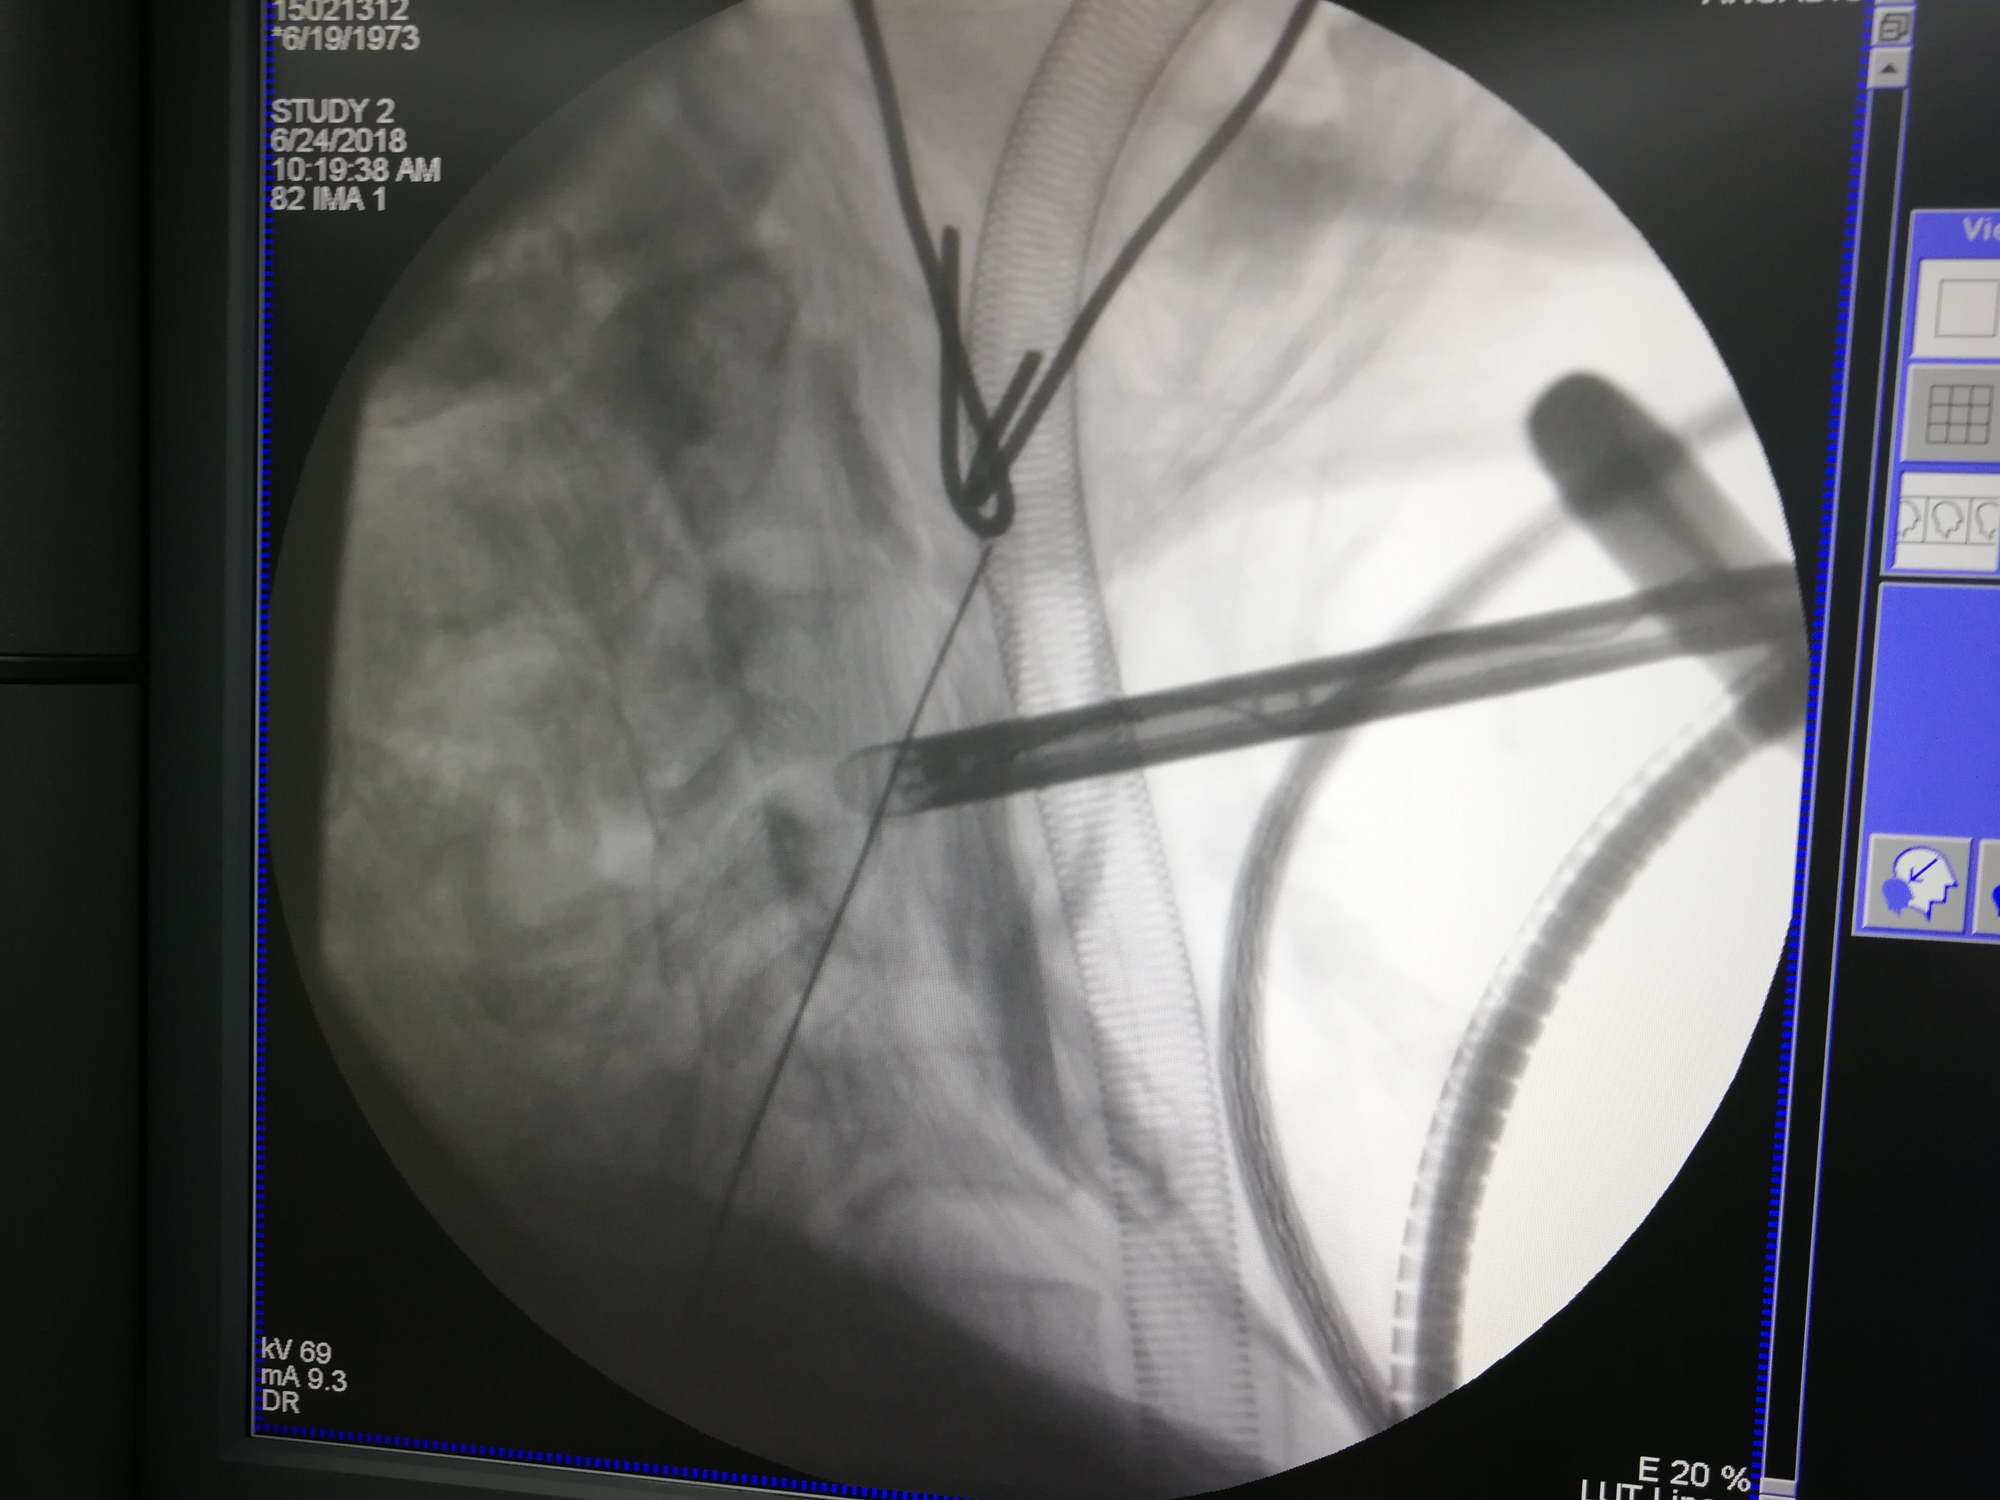

经刘维克专家团队检查讨论后,认为此病例是C3/4椎间盘向后巨大突出(中央型)是引起患者症状的根源,鉴于颈后路无法处理中央型突出,充分与患者及其家属沟通后,决定行颈前路经皮脊柱内镜微创手术治疗。麻醉方式选择:全身麻醉。颈前部解剖结构复杂,建立通道时必须避开气管、食管,选择全身麻醉行气管、食管插管透视时可显影,有效的降低手术对重要器官的损伤。在C臂透视下完成脊柱内镜安放,成功取出突出椎间盘,射频刀头仔细止血,修复破损的纤维环,术后只有7毫米的微小创口。患者卧床24小时后,即可佩戴颈托下床活动,头晕不适症状基本消失。病人对立竿见影的疗效非常满意。

术中建立工作通道

术中工作通道术中影像

术中安放颈椎内镜

术中摘除突出髓核